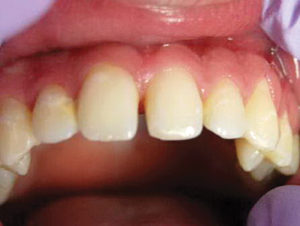

Caso 4

Este adolescente de 16 años tuvo una recaída post-ortodoncia de un diastema de la línea media y era consciente del espacio. Se dieron opciones para cerrar el espacio, incluyendo seis meses de corrección de ortodoncia versus corrección restaurativa con restauraciones directas. Debido a la forma larga y delgada de sus incisivos centrales, el paciente, su madre y yo acordamos que la mejor opción sería la corrección restauradora.

Figura 1. Foto preoperatoria de un diastema de 2.75 mm en un adolescente preocupado (recaída post ortodóntica). |

Figura 2. Después de la colocación de dos matrices Bioclear, los dientes se biselaron ligeramente, se grabaron con ácido y se unieron con Scotchbond Universal. Activa Bioactive Restorative A2 fue colocado y curado. Las restauraciones de los dientes fueron terminadas y pulidas. |

Figura 3. Cuando uso Activa, se notó una naturaleza de mezcla y camaleón del material. Por lo general, combina maravillosamente con el esmalte cuando se coloca como una restauración de un tono en la parte anterior. Se colocó un retenedor fijo 1-1 después de las restauraciones para evitar recaídas adicionales. |